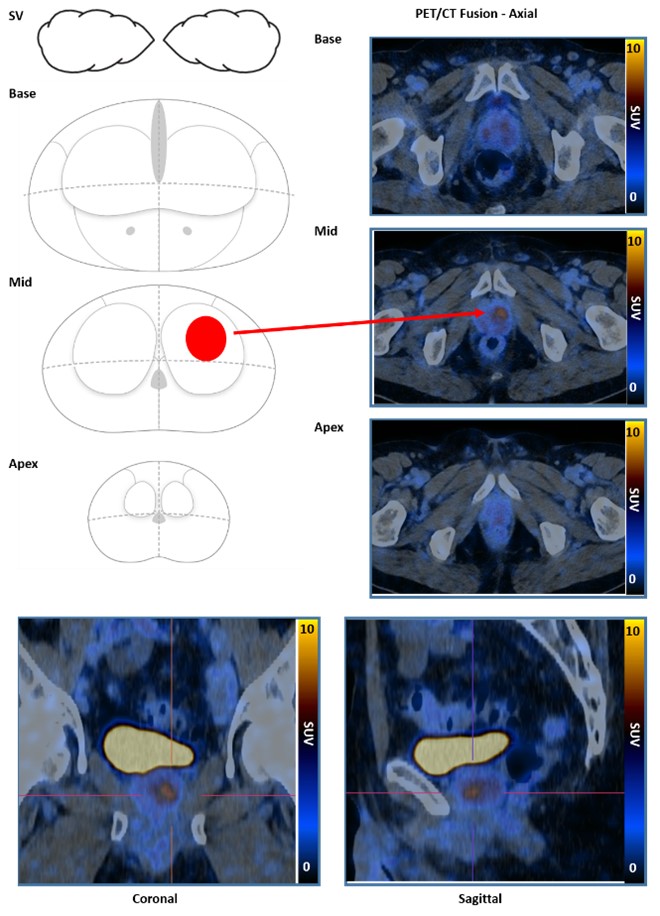

PRIMARY score

The PRIMARY score is a 5-category scale developed to identify clinically significant intraprostate malignancy (csPCa) on 68Ga-prostatespecific membrane antigen (PSMA) PET/CT (68Ga-PSMA PET) using a combination of anatomic site, pattern, and intensity.